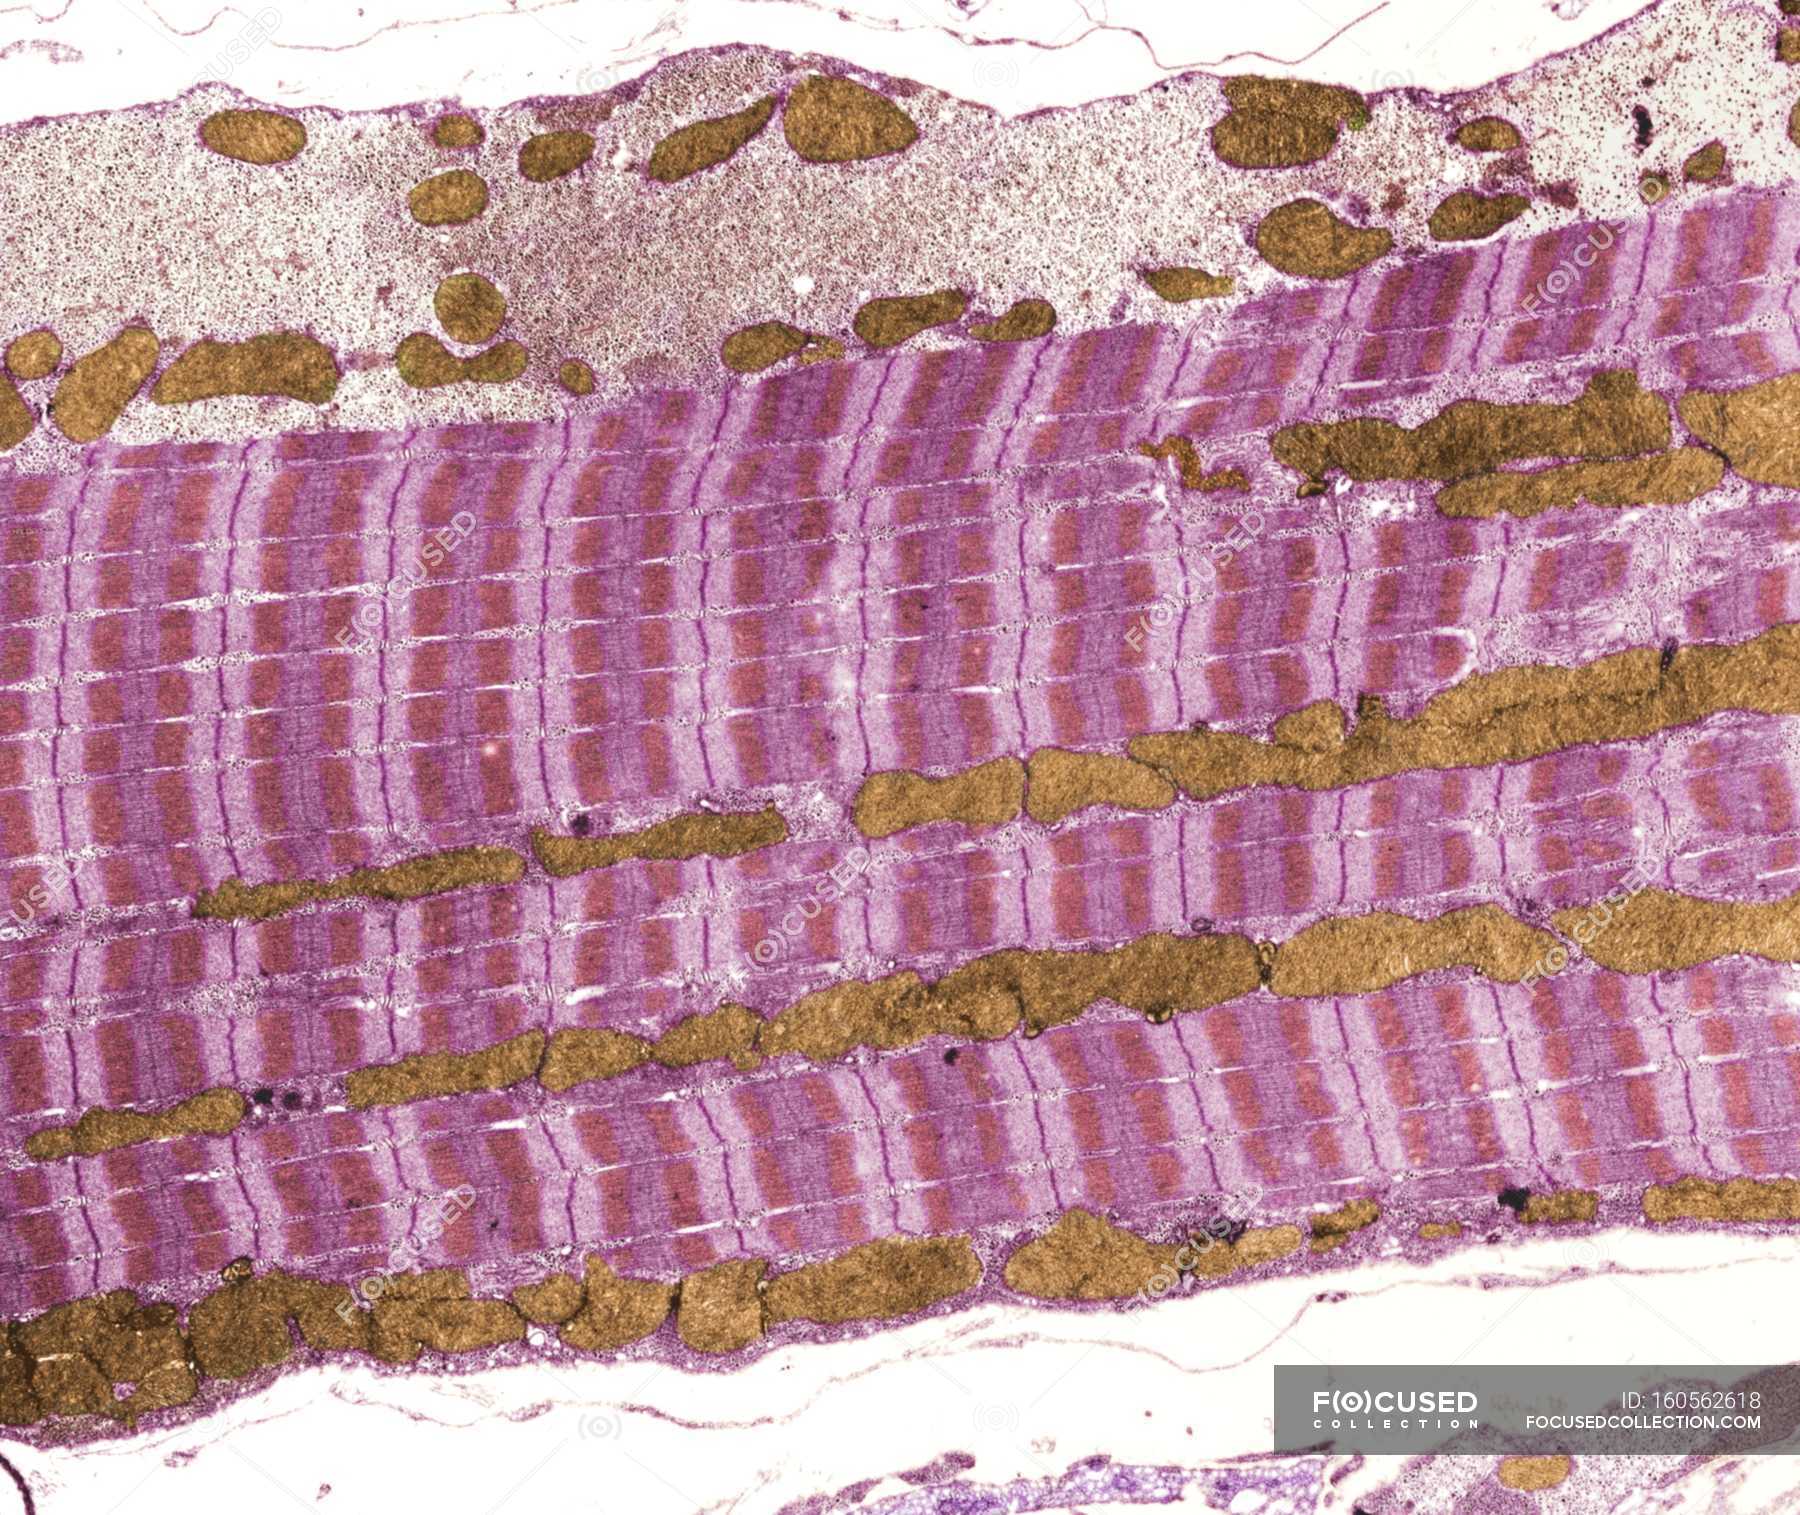

Молочная кислота в мышцах - это обычное явление, которое происходит в результате физических нагрузок. Она образуется в мышцах во время интенсивных тренировок, когда организм не может обеспечить достаточное количество кислорода для процесса окисления глюкозы. Это приводит к накоплению молочной кислоты в мышцах, что может вызвать ощущение жжения и усталости.

Молочная кислота может вызвать ощущение усталости и дискомфорта в мышцах во время и после тренировки. Однако, это является естественной реакцией организма на интенсивные нагрузки. Со временем мышцы адаптируются к процессу накопления молочной кислоты, что позволяет улучшить выносливость и способствует росту мышечной массы.